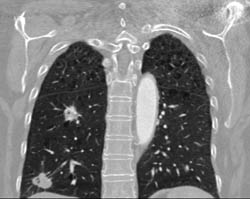

Aortic Valve Replacement With Aortic Root Repair